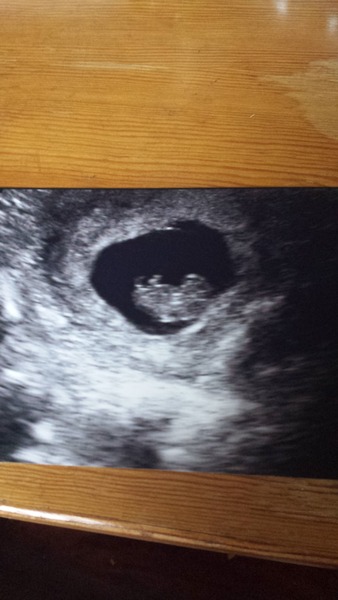

Ooh, lots of scan sharing! Exciting!

Here is mine, apparently flump was wiggling but I couldnt really make it out. All is well anyway, phew!